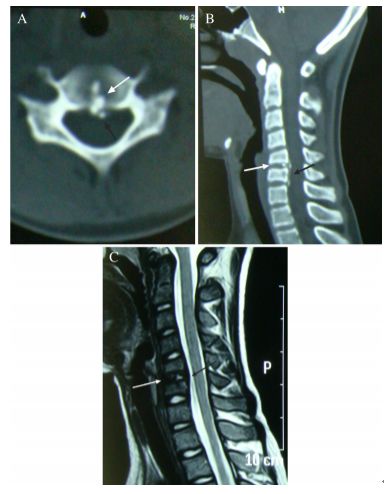

一位88岁女性患者,主诉急性颈痛伴发热2个月入院。体温波动在38-39.3℃,无视力模糊,无神经及脊髓压迫征象。颈椎CT+矢状位重建显示寰椎横韧带的曲线状钙化(图A,箭头所示),线性钙化(图B,箭头所示),以及齿状突周围的冠状钙沉积(图C,箭头所示)。给予短期非甾体抗炎药和泼尼松龙(15mg/d)后,其上述症状完全缓解。同时,作者指出这类疾病通常不需要长期用药。